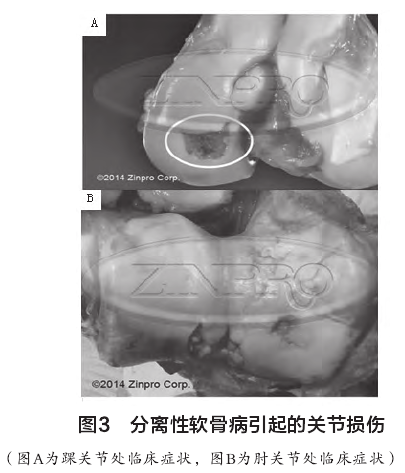

DrCarlson解釋道:“雖然亞臨床的現(xiàn)象相當普遍,這些病變的很大一部分能完全愈合。多數(shù)情況下,骨能夠形成繞開壞死軟骨的區(qū)域,起到愈合作用?!钡牵绻浌墙M織超過所承受的壓力出現(xiàn)塌陷,軟骨病臨床癥狀惡化,往往造成跛行和疼痛。圖3為軟骨病臨床惡化癥狀,壞死軟骨組織表面出現(xiàn)裂縫。根據DrCarlson介紹,軟骨血液供應受阻導致軟骨細胞死亡的確切原因是未知的,然而,眾所周知,管理和環(huán)境因素引起的創(chuàng)傷會導致亞臨床病變進一步演變成軟骨病。